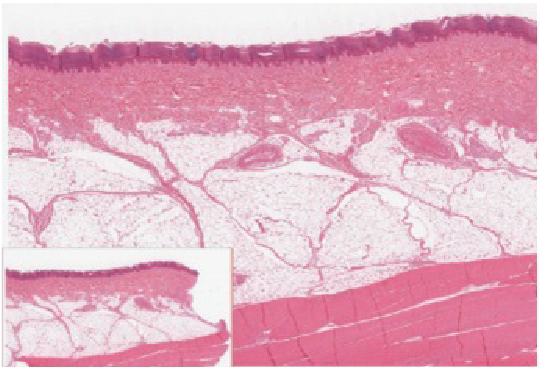

Thin Skin versus Thick Skin

Figure 1.2 – Thin Skin versus Thick Skin: These slides show cross-sections of the epidermis and dermis of (a) thin and (b) thick skin. Note the significant difference in the thickness of the epithelial layer of the thick skin. From top, LM × 40, LM × 40. (Micrographs provided by the Regents of University of Michigan Medical School © 2012)